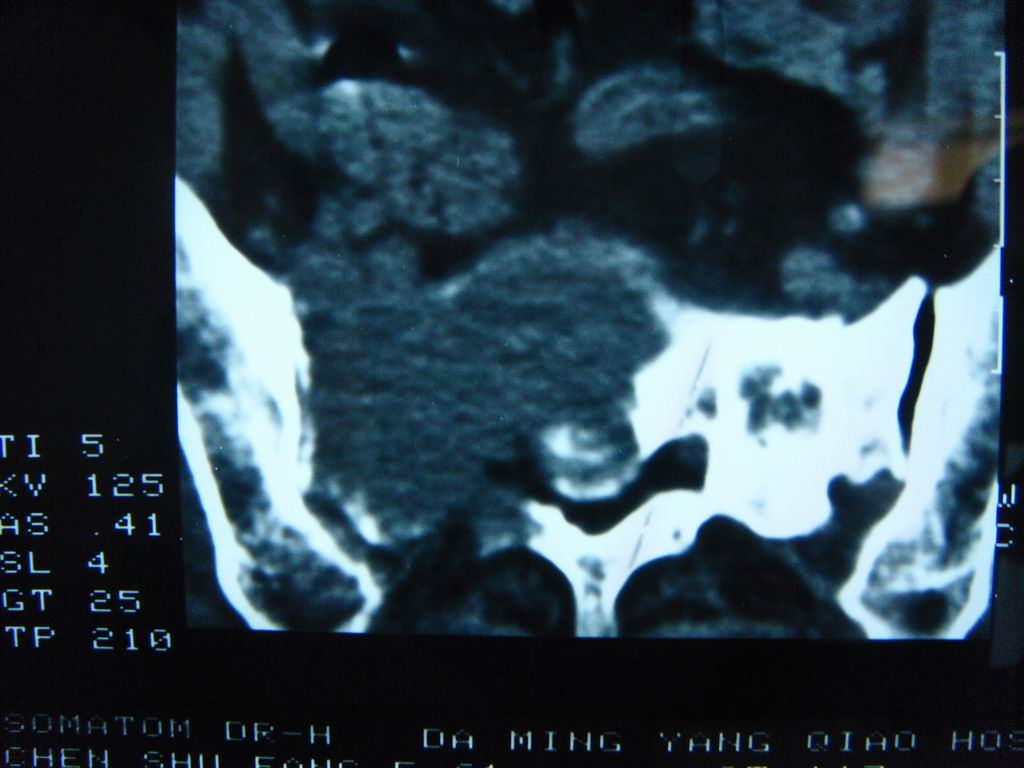

标题: CT21430:女性65岁 乳腺癌术后3年 [打印本页]

标题: CT21430:女性65岁 乳腺癌术后3年

结合病史,考虑骶骨转移瘤,但软组织肿块未突破骨壳,骨巨细胞瘤不能完全排除,骨髓瘤及脊索瘤不考虑。

结合病史,考虑骶骨转移瘤。

结合病史,考虑骶骨转移瘤。其它椎体,如腰5是否有问题呢?

个人感觉骨巨细胞瘤可能性大些。